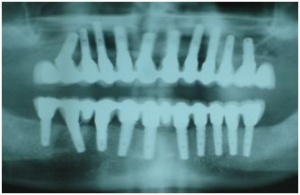

Il s'agit de la réalisation prothétique de deux bridges complets maxillaire et mandibulaire sur implants dont la phase chirurgicale est actuellemnt sur le site en vidéo.

-la réalisation des piliers implantaires